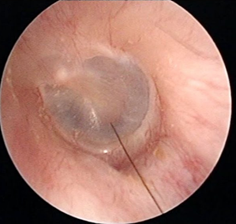

耳道里的皮肤是很敏感、很脆弱的,一不小心就容易擦伤耳道壁、损伤鼓膜、戳伤鼓膜造成穿孔。

至于那些往耳朵里灌牛奶、塞竹签的迷幻采耳操作,强烈建议大家不要尝试。否则你很可能喜提“外耳道炎”“鼓膜穿孔”等耳鼻喉科急诊套餐……

另一方面,如果小概率情况真的发生在你身上,因耳垢栓塞引发听力障碍、耳痛、耳鸣、耳堵塞感等症状,那确实是得掏。

但不是让我们自己掏,而是要去医院耳鼻喉科请医生做专业的诊断,再用专业的器材小心地取出来,必要时还需要配合其它治疗。